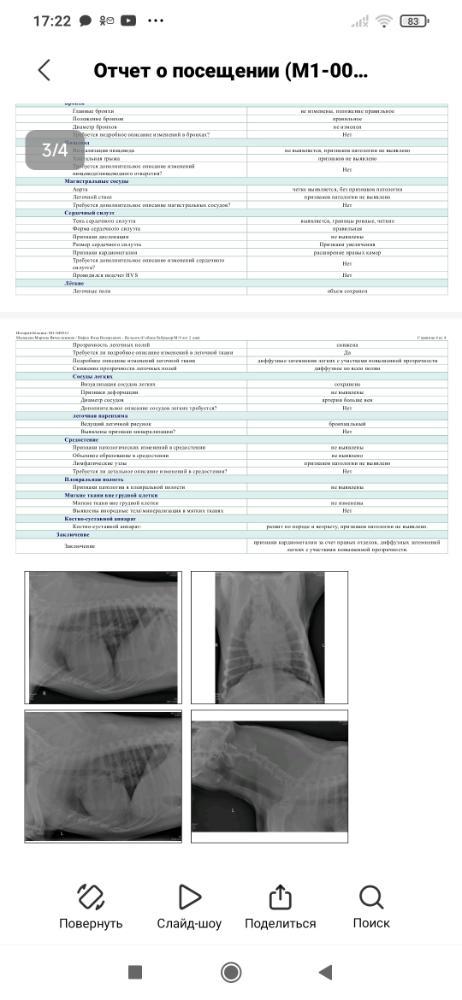

Нельсон приболел - бронхопневмония(( Предстоит поездка к кардиологу. В теме минус 14851р.((( Просим помощи!!! 🙏 Куратор Вячеславовна